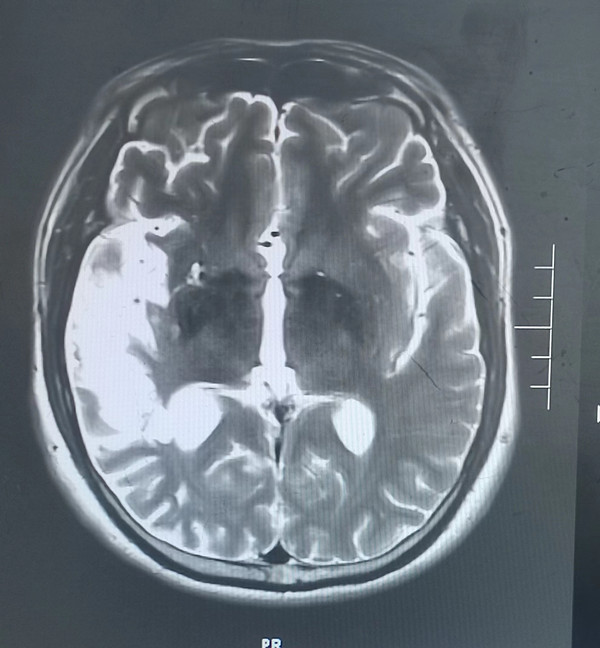

5月前46歲的徐先生因患腦梗死在西安某醫(yī)院就診,經(jīng)治療后好轉(zhuǎn),近1周再次出現(xiàn)腦梗死癥狀來我院就診,腦梗死導(dǎo)致他視野缺損,左上肢肢體無力,入院后檢查頭顱磁共振檢查發(fā)現(xiàn)右側(cè)顳葉大面積腦梗死,由于錯過溶栓機會,目前只能保守治療,徐先生一家郁悶至極,平時無高血壓、無糖尿病、高血脂等疾病,他按時服用藥物治療,他只是偶爾吸煙,為何反復(fù)出現(xiàn)腦梗死?

入院后經(jīng)追問病史患者在37歲時還患有急性心肌梗死病史,當(dāng)時急診溶栓后病情好轉(zhuǎn)。為明確患者反復(fù)出現(xiàn)腦梗死、心肌梗死原因,入院后神經(jīng)內(nèi)科張醫(yī)生為患者做了TCD發(fā)泡試驗,發(fā)現(xiàn)有明顯異常,經(jīng)食道超聲檢查發(fā)現(xiàn)患者心臟有先天性房間隔缺損。為明確患者心梗原因,我們先行冠狀動脈造影并未發(fā)現(xiàn)有嚴重冠脈狹窄病變,經(jīng)我院吳棟梁院長及崔旭輝主任介入團隊再次評估后考慮患者屬于典型的房間隔缺損出現(xiàn)反常栓塞病案。